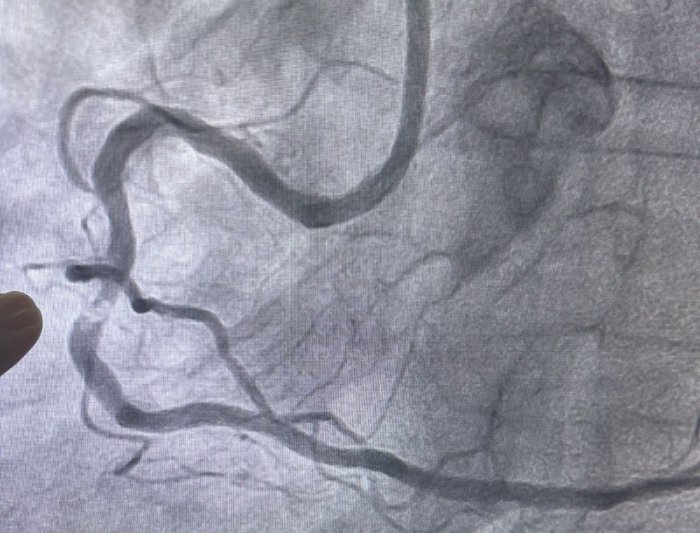

Realizado pelos cardiologistas intervencionistas Thiago Lisboa e Glauco Gusmão, o procedimento atendeu um paciente que apresentava dor torácica e falta de ar limitantes, com importante impacto na qualidade de vida. O cateterismo cardíaco evidenciou uma obstrução de 90% em uma artéria coronária, associada a uma placa extremamente calcificada (descrita como um verdadeiro "bloco de cálcio", conforme evidenciado nas imagens do exame), cenário em que as técnicas convencionais de angioplastia apresentam maior limitação técnica. Após o procedimento realizado com sucesso, o paciente recebeu alta hospitalar em menos de 24 horas.